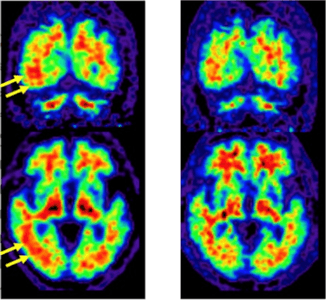

左:従来PEF/CT装置により得られた脳アミロイドPET画像

黄色矢印の部分で灰白質にアミロイドの分布を示すPET薬剤集積がひろがっているようにみえ(赤い部分が脳の表面までひろがっている)、同部にアミロイドが蓄積していると判定された。

右:本装置により得られた脳アミロイドPET画像

従来PET/CT装置でアミロイド蓄積陽性と判定された部分について、灰白質まで集積が及んでいないことが明白である(赤い部分は脳の表面まで達していない)。

また、これまで脳アミロイドPET検査においては、灰白質への集積が曖昧で、判定に苦慮する症例が約1割あるといわれてきました。今回の検証では、17例中1例の患者において、従来型PET/CT装置で、右側頭葉にアミロイド沈着が確認されました。読影指針※8 に従えば、アミロイド沈着陽性(アルツハイマー病理が存在する)と診断されるものです。しかし、本PET装置による画像では、右側頭葉を含めたどの部位にもアミロイド沈着はなく、陰性と判定され、診断が変更されることになりました。